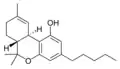

Let's start with some background on marijuana chemistry. Relevant chemicals in marijuana fall into two broad classes: cannabinoids (which in plants are specific to the Cannabis genus) and terpenoids (which are widespread in many plants).[7][8] Humans and other animals, produce endocannabinoids, which are different than but in the same chemical class as those cannabinoids found in cannabis. The main psychoactive chemical in marijuana is tetrahydrocannabinol (THC). Another important cannabinoid is cannabidiol (CBD), which is not psychoactive but has many claimed health benefits. Terpenoids in cannabis include ocimene, myrcene, β-caryophyllene, limonene, pinene, myrcene, linalool.